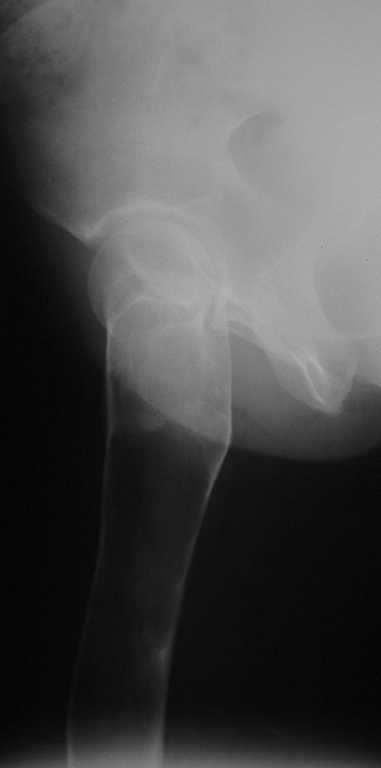

Уважаемые коллеги! В клинику поступила молодая женщина 35 лет с жалобами на интенсивные боли в области правого бедра, носят спонтанный характер, имеются "ночные" боли.

Движения в правом тазобедренном суставе в полном объёме, практически безболезненные. По результатам x-ray диагностики выявлен патологический очаг, занимающий весь проксимальный отдел и 2/3 диафиза правой бедренной кости. Другие трубчатые кости верхних и нижних конечностей - без очагов поражения.

Имеется небольшой (1,5х2,5 см) очаг в крыле правой подвздошной кости.

По результатам трепанобиопсии проксимального отдела правой бедренной кости - фиброзная строма и костные балки, без атипии.